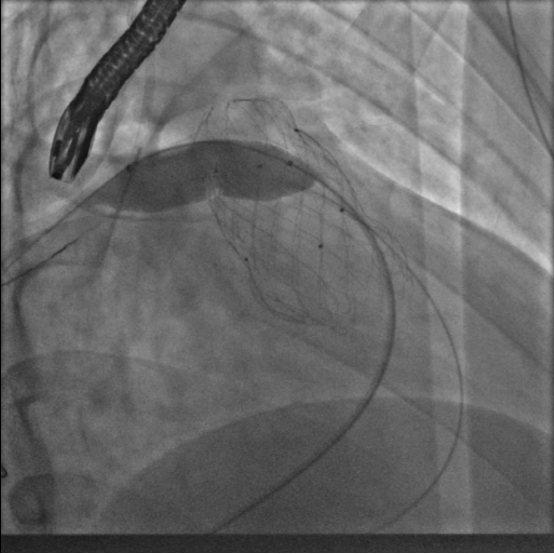

10月10日,葛均波院士、周达新教授团队转播了一台高难度的经导管肺动脉瓣置换术(PPVI),患者为法洛四联症纠治术并发肺动脉瓣反流患者。为防止患者右心功能障碍进一步恶化,团队决定为其行PPVI。术中考虑到患者肺动脉分叉较短,存在瓣膜释放后移位风险,故选择高位释放法。但释放瓣膜后造影提示右肺动脉开口局部被阻挡。

在先后尝试Snare圈套瓣架下缘下拉法、双导管圈套瓣架上缘下拉法,但效果不理想。团队迅速调整方案,创新性的采用Snare圈套住主路的Lunder quist导丝,建立球囊输送轨道,

如此球囊顺利通过瓣膜支架网孔进入右肺动脉,在DSA指引下逐步扩张球囊,成功使人工瓣膜支架向右心室侧移位。复查造影提示右肺动脉开口未见明显阻挡,跨右肺动脉压差小于8mmHg。复查肺动脉主干造影,显示人工瓣膜启闭良好,轻微瓣膜反流。最终手术疗效显著、取得令人满意的结果。肺瓣植入阻挡肺动脉是少见并发症,本例采用了多种技术,最终完美解决问题,为此类病人处理提供了很好经验参考。